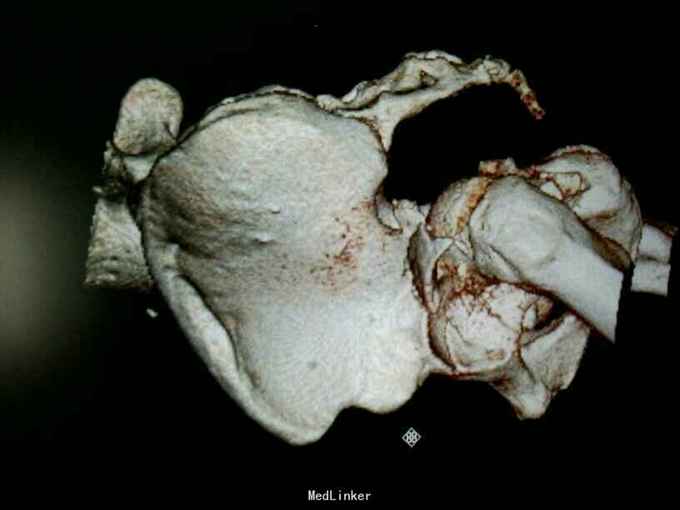

专科情况:患者平车推入病房,左股骨髁上骨牵引中,左髋部压痛、叩击痛(+),左髋关节主动活动受限,被动活动可引起明显疼痛,骨盆挤压、分离试验(-),脊柱、余肢体无畸形及压痛、叩击痛,关节无红肿、活动自如。双侧膝、跟腱反射正常,双侧Babinski征阴性。 辅助检查:骨盆三维重建CT示:左侧髋臼及耻骨下支骨质不连续,见多发不规则形骨折线,骨折断端错位成角,可见多发游离骨片,股骨头向后移位,其周软组织肿胀。